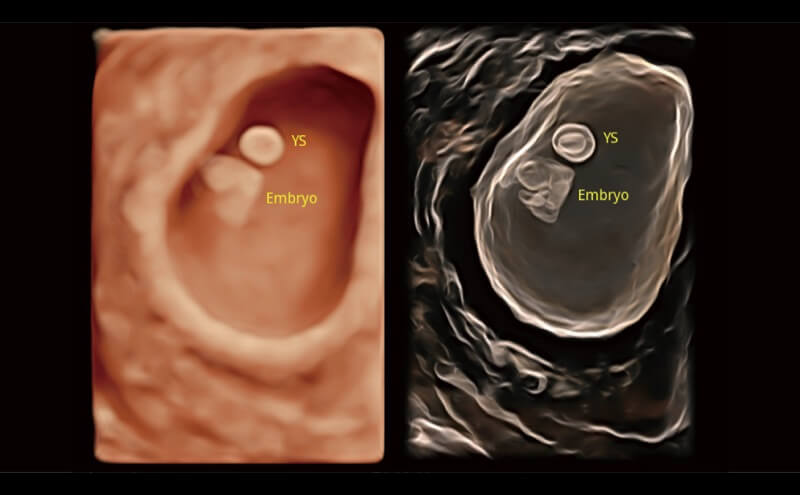

Basierend auf einem verlässlichen Deep-Learning-Algorithmus für Big Data ist S-Fetus eine brillante Komplettlösung für automatische Standard-Ebenen-Erfassung und Messung. Mit nur einem Klick werden gängige fetale Biometrie-Ergebnisse mit hoher Intelligenz, Genauigkeit und Effizienz erzielt, um einen beispiellosen Bedienungskomfort zu gewährleisten.

Dank der Unterstützung von Auto OB wird eine schnelle und hoch effiziente fetale Biometrie erreicht. Gleichzeitig kann diese auf Deep Learning basierende Methode zu konsistenteren Ergebnissen führen und die Variabilität, die vom Anwender abhängig ist, effektiv reduzieren.

Die Visualisierung des 3D-Gesichts des Fetus ist wichtig für die Diagnose von Gesichtsanomalien. Durch Auto Face können Hindernisse und Artefakte wie Nabelschnur, Plazenta, Gebärmutter und Extremitäten einfach entfernt werden, um eine optimale Ansicht des fetalen Gesichts zu erhalten.